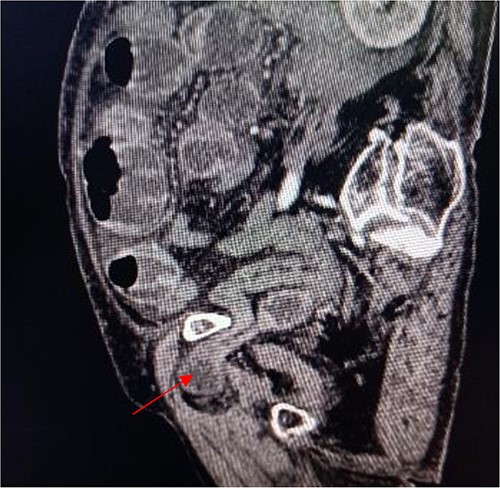

Sagittal view shows a right obturator hernia (indicated by red arrow).

An 86-year-old female complained of constipation with abdominal pain, nausea, and vomiting for ˃2 weeks. The patient had defecated once, after conservative treatment with an enema in a local hospital, with less abdominal pain and no nausea or vomiting; hence, she was admitted to our hospital for further diagnosis and treatment. The patient’s body temperature was 36.8°C, pulse rate was 87 beats/min, respiration rate was 18 breaths/min, and blood pressure was 125/76 mmHg. The patient was conscious and had a thin appearance, and physical examination indicated that the abdomen was soft, and without tenderness and rebound pain. Routine blood examination showed that hemoglobin was 87 g/L and hematocrit was 28.3%. Abdominal computed tomography revealed the right lower abdominal small intestine protruding into the femoral triangle through the obturator; the upstream intestine was distended and expanded, and multiple fluid levels were observed in the intestinal lumen. Multiple lymph nodes were noticed in the abdomen and retroperitoneum; the large ones had a diameter of ~1 cm. Uneven thickening and enhancement of the local ascending colon were noted.